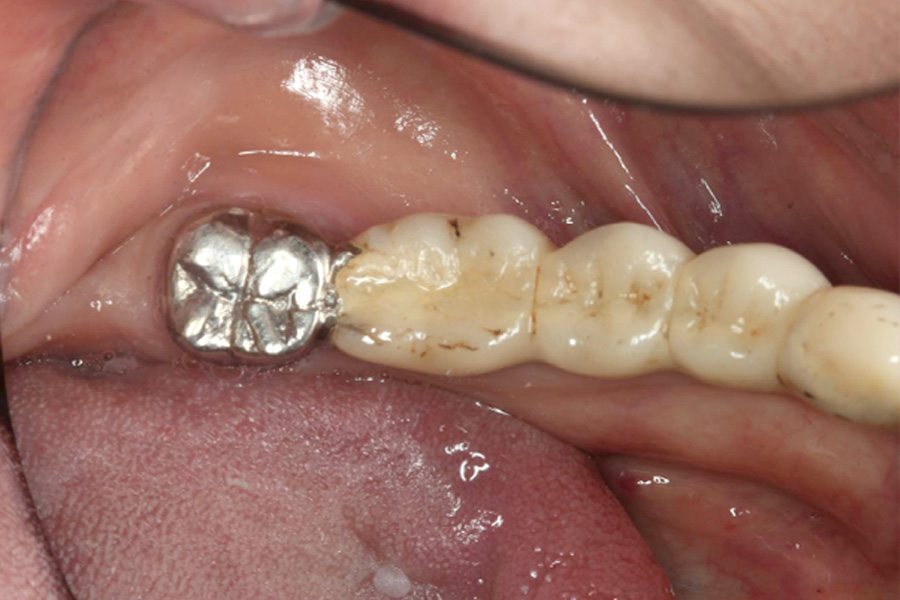

治療後

治療後症例写真

ブリッジの土台にしていた歯の保存ができなくなり、再治療を行いました。

右下3番、7番の抜歯後、右下3番、5番、6番相当部分にインプラントを3本埋入し、補綴を行いました。

治療期間

(治療回数)

約10ヶ月

治療費 約200万円

治療回数 12回

治療内容 右下奥歯抜歯、インプラント埋入(3本)